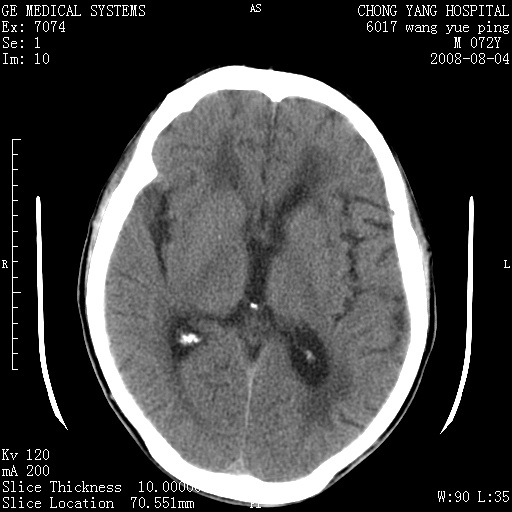

标题: CT14987:M72Y,头痛头昏,BP220/110. [打印本页]

标题: CT14987:M72Y,头痛头昏,BP220/110.

1)考虑左侧小脑脑梗塞。2)脑白质病。3)脑萎缩。4)双侧鼻腔新生物(息肉?)并阻塞性副鼻窦炎。

1.左侧小脑大面积梗塞;2.左侧基底节区腔梗;3.白质疏松;4.脑萎缩;5.慢性副鼻窦炎

小脑左侧病灶呈扇形分布,增强后未见明显瘤体样节结影,病变区未见强化。

支持:左侧小脑脑梗塞梗塞表现

另:脑白质病。脑萎缩。双侧鼻腔新生物(息肉?)并阻塞性副鼻窦炎。

1)考虑左侧小脑脑梗塞,建议治疗后复查除外其他,左基底节区腔隙性脑梗塞2)脑白质变性3)脑萎缩。4)双侧鼻腔新生物(息肉?)并阻塞性副鼻窦炎。